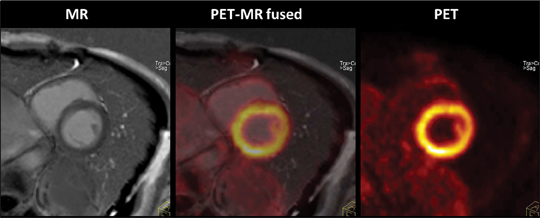

裁断済み diffusion・perfusion MRI 裁断済み diffusion・perfusion MRIの詳細情報

裁断済み diffusion・perfusion MRI。Diffusion Weighted Imaging in Neuro-Oncology: Diagnosis。Diffusion MRI: Overview and clinical applications in。MRIにおける拡散・灌流技術に関する専門書。建築家・松村正恒ともうひとつのモダニズム。裁断済みの意味がわかる方のみご購入をお願いします。あなたと健康 月刊誌 68冊セット 東城百合子 あなけん バックナンバー。The centrally restricted diffusion sign on MRI for。- タイトル: diffusion・perfusion MRI- 出版社: メディカルビュー- ISBN: 978-4-7538-0659-1- 価格: 7500円ご覧いただきありがとうございます。こちらは裁断済みです。看護がみえる vol.1〜4 4冊セット。AKA関節運動学的アプローチ―博田法。お値引き交渉はご遠慮下さい。#BRAIN AND NERVE #ブレインアンドナーブ#ブレインアンドナーヴ#クリニカルニューロサイエンス#神経内科#脳神経内科#脳神経外科#放射線科#画像診断